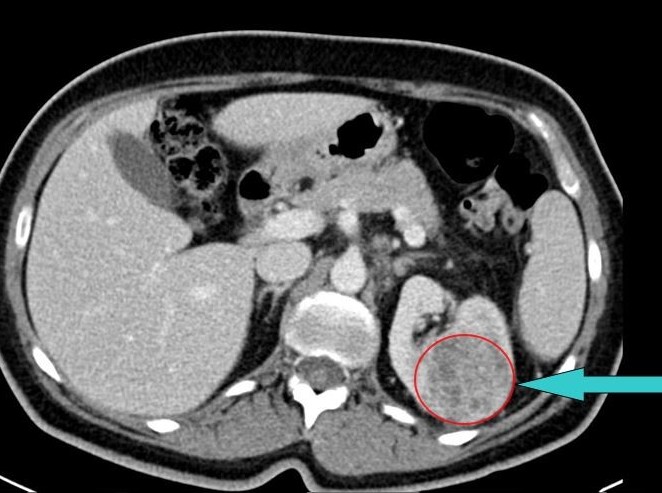

Muž 58 let – světlobuněčný karcinom

Na vyšetření přišel 58letý Jan Vokřálek, který byl předtím vyšetřen praktickým lékařem (PL). Pacient již 3 dny trpí trvajícím otokem pravé dolní končetiny, praktický lékař mu zjistil suspektní tromboflebitidu. Dále trpí dyspeptickým syndromem. Lumbalgií netrpí, hematurii neguje.